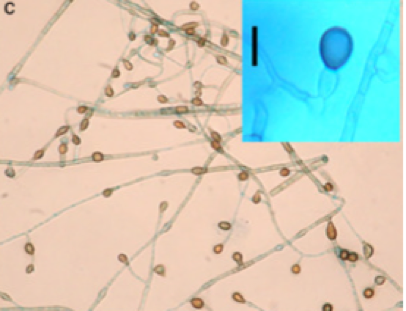

First case of chromoblastomycosis due to Phoma insulana Primer caso de cromoblastomicosis causado por Phoma insulana

Chromoblastomycosis